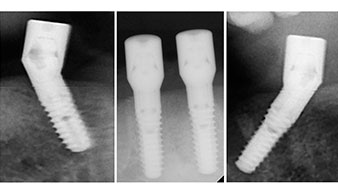

El protocolo quirúrgico de los implantes utilizados (SKY, bredent medical) prescribe una velocidad de 1 200/rpm para las perforaciones piloto (figs. 7-9).

Este valor se corresponde con la posición siguiente del ajuste predefinido en Implantmed. Aquí se aprecia la inclinación de aproximadamente 45 grados del contra-ángulo de W&H hacia medio caudal en la región de la pieza 45 para preservar el nervus mentalis. El foramen mentale sirve como orientación anatómica para todas las perforaciones en esta zona. Las perforaciones siguientes se realizaron con una velocidad reducida de 300/rpm (figs. 10 y 11).

El siguiente ajuste programado es la propia inserción de los implantes. En nuestra clínica, solemos insertar los implantes con una fuerza de 32 Ncm de manera estándar (figs. 12 y 13).

El requisito imprescindible para el tratamiento inmediato es una alta estabilidad primaria. Para satisfacer dicho requisito, en este caso, se prescindió del corte de rosca. La unidad de accionamiento Implantmed de W&H empleada aquí, posee un modo propio para ello que también puede seleccionarse directamente y resulta imprescindible para muchas indicaciones. Los últimos giros para la inserción del implante superaron el valor de 32 Ncm, por lo que se realizaron manualmente. En tales casos, se recomienda utilizar la función autocortante de los implantes y girar el implante varias veces hacia delante y hacia atrás de forma que el implante se aproxime gradualmente hasta su posición definitiva sin ejercer una presión excesiva sobre el hueso (fig. 14).

Tanto el contra-ángulo como la pieza de mano S-11 de W&H disponen de refrigeración externa, lo que supone una ventaja, ya que la solución de NaCl llega exactamente al lugar preciso y, en caso necesario, también puede reajustarse. Los contra-ángulos y las piezas de mano pueden desmontarse, lo que resulta muy recomendable desde el punto de vista higiénico y de la capacidad de esterilización. Se implantaron cuatro implantes SKY de 4,0 x 14 mm. Los contra-ángulos y las piezas de mano pueden desmontarse, lo que resulta muy recomendable desde el punto de vista de la higiene y de la capacidad de esterilización. Se implantaron cuatro implantes SKY de 4,0 x 14 mm.